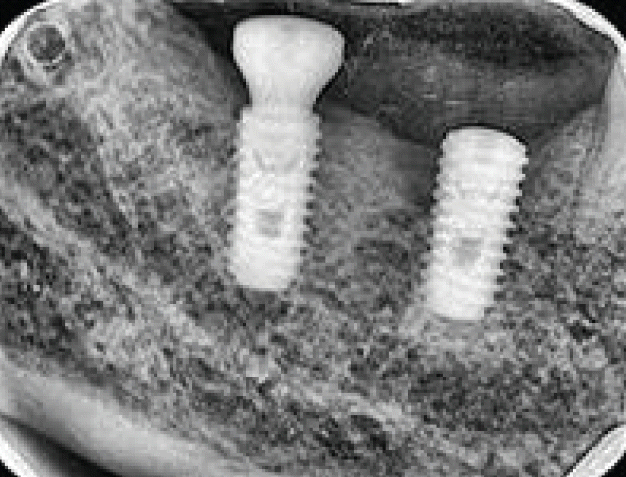

모든 치주진료는 치석제거술이 먼저 시행되어야한다. 임플란트 8주위염도 마찮가지이다. 반드시 본원에서 시행될 필요는 없으며 최근에 타원에서 시행된 경우에는 내역설명이 필요하다. 이미 보철이 진행된 곳에 환형의 치조골소실이 발생된 경우에(Fig. 8) 치석제거와 함께 보철을 제거하고 cover screw 를 연결해주면 연조직이 치유된다(Fig. 9). 이후에 치조골결손부골이식술을 시행하고(Fig. 10) 일정기간 치유가 이루어진 후 다시 임플란트를 노출(치은박리소파술 적용)하여 치유지대주를 연결하고 재보철을 함으로서 임플란트를 재생하여 다시 사용해볼 수 있는 술식을 건강보험항목으로 진행할 수 있다.

치주질환등으로 치과임플란트에 차107치조골결손부골이식술이나 차108조직유도재생술을 적용할 수 있다[8,9]. 이 두 술식은 굉장히 헷갈리는 술식이기도 하다. 둘다 골이식이 이루어지는 것이지만 차107 치조골결손부골이식술은 자가골이나 동종/이종골이 반드시 사용되어야한다. 반면에 차108조직유도재생술은 차폐막(membrane)의 사용이 반드시 필요하며 골이식은 시행될 수도 있고, 시행되지 않을 수도 있다. 이 둘 술식에 사용되는 동종/이종골은 반드시 보험등록이 가능한 재료이어야하며 술식이전에 건강보험심사평가원에 사전 등록되어 있어야 한다. 차폐막도 보험등재된 재료가 사전에 등록되어야 한다.- 10. 상악동 이물제거술(신설. 2026년 3월 1일)